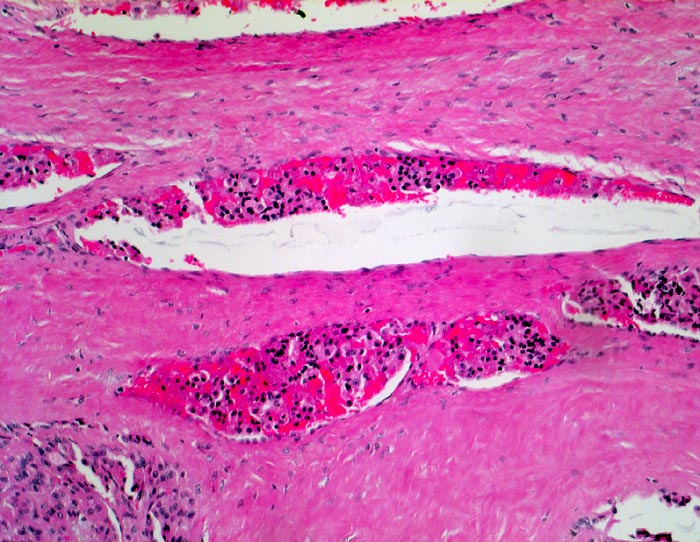

PathoPic – image database / PathoPic ID 4953 - Follikuläres Schilddrüsenkarzinom: Gefässeinbruch

Follikuläres Schilddrüsenkarzinom: Gefässeinbruch

maligner Tumor

Schilddrüse

Klinik

Histologie

100